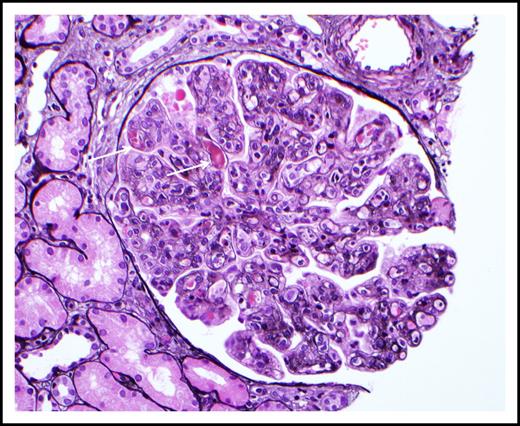

Signs and symptoms are generally associated with vascular occlusion by the cryoprecipitate, although small-vessel vasculitis features may also be seen (eg, purpura, glomerulonephritis, neuropathy). Two studies (64 patients each) reported on the clinical manifestations in type I cryoglobulinemia.5,6 Skin manifestations were the most common and were observed in 69% to 86% of patients. These manifestations include purpura, livedo reticularis, Raynaud's phenomenon, acrocyanosis, skin necrosis, ulcers and, infrequently, digital gangrene. Cutaneous manifestations are often confined to acral sites (distal limbs, nose, and ears) and can be triggered by cold exposure. Skin necrosis (Figure 2) is evident in approximately one third of patients and is mainly seen in the lower extremities in the supramalleolar areas. These ulcers do not heal easily because of impaired blood supply, they put patients at significant risk for sepsis, and at times require amputation. Extracutaneous disease includes peripheral neuropathy in 19% to 44% of patients, arthralgia in 28%, and renal disease in approximately 30%. Painful peripheral neuropathy is usually confined to the lower extremities with predominant sensory impairment, but motor involvement can also be seen. Renal involvement presents as proteinuria, microscopic hematuria, increased creatinine, and/or hypertension and is more common in IgG than IgM cryoglobulinemia.5 Most renal biopsies show membranoproliferative glomerulonephritis (MPGN) with immune cell infiltration, glomerular thrombi, and microtubular deposits composed of the cryoglobulin aggregates (Figure 3).

Cryoglobulinemic glomerulonephritis. The glomerulus shows global occlusion of peripheral capillary lumina by numerous infiltrating monocytes. Segmental intracapillary pink-staining immune thrombi (arrows), likely representing cryoglobulin deposits, are seen. There is widespread duplication of the glomerular basement membrane with associated cellular interposition (silver stain). Original magnification ×400. Photo courtesy of Samih Nasr, Mayo Clinic, Rochester, MN.